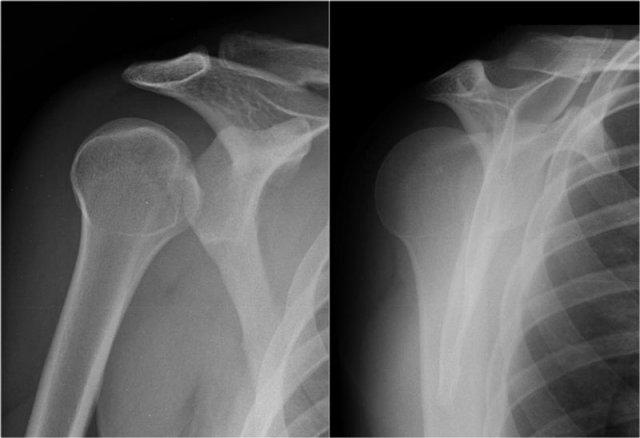

Bankart xương

Tổn thương Bankart kèm mảnh xương là phát hiện thường gặp ở bệnh nhân trật khớp ra trước và thường được nhìn thấy trên X-quang hoặc CT.

Trên MRI khớp cản từ, việc xác định mảnh xương có thể gặp khó khăn.

Trên CT, mảnh xương ở phía trước ổ chảo dễ dàng được nhận diện (mũi tên).

Cuộn qua các hình ảnh.

Có tổn thương Bankart xương (mũi tên đỏ cong).

Đường rách lan lên trên (mũi tên đen).

Ngoài ra còn có khuyết Hill-Sachs (mũi tên đỏ).

Hình MRI khớp cản từ mặt phẳng đứng dọc cho thấy sự lan rộng lên trên của đường rách Bankart.

Đây là một bệnh nhân khác có Bankart xương được thấy trên bốn hình ảnh liên tiếp của MRI khớp cản từ ở tư thế ABER.

Lưu ý đường viền bất thường của ổ chảo phía trước và bờ trước bị avulsion (mũi tên)